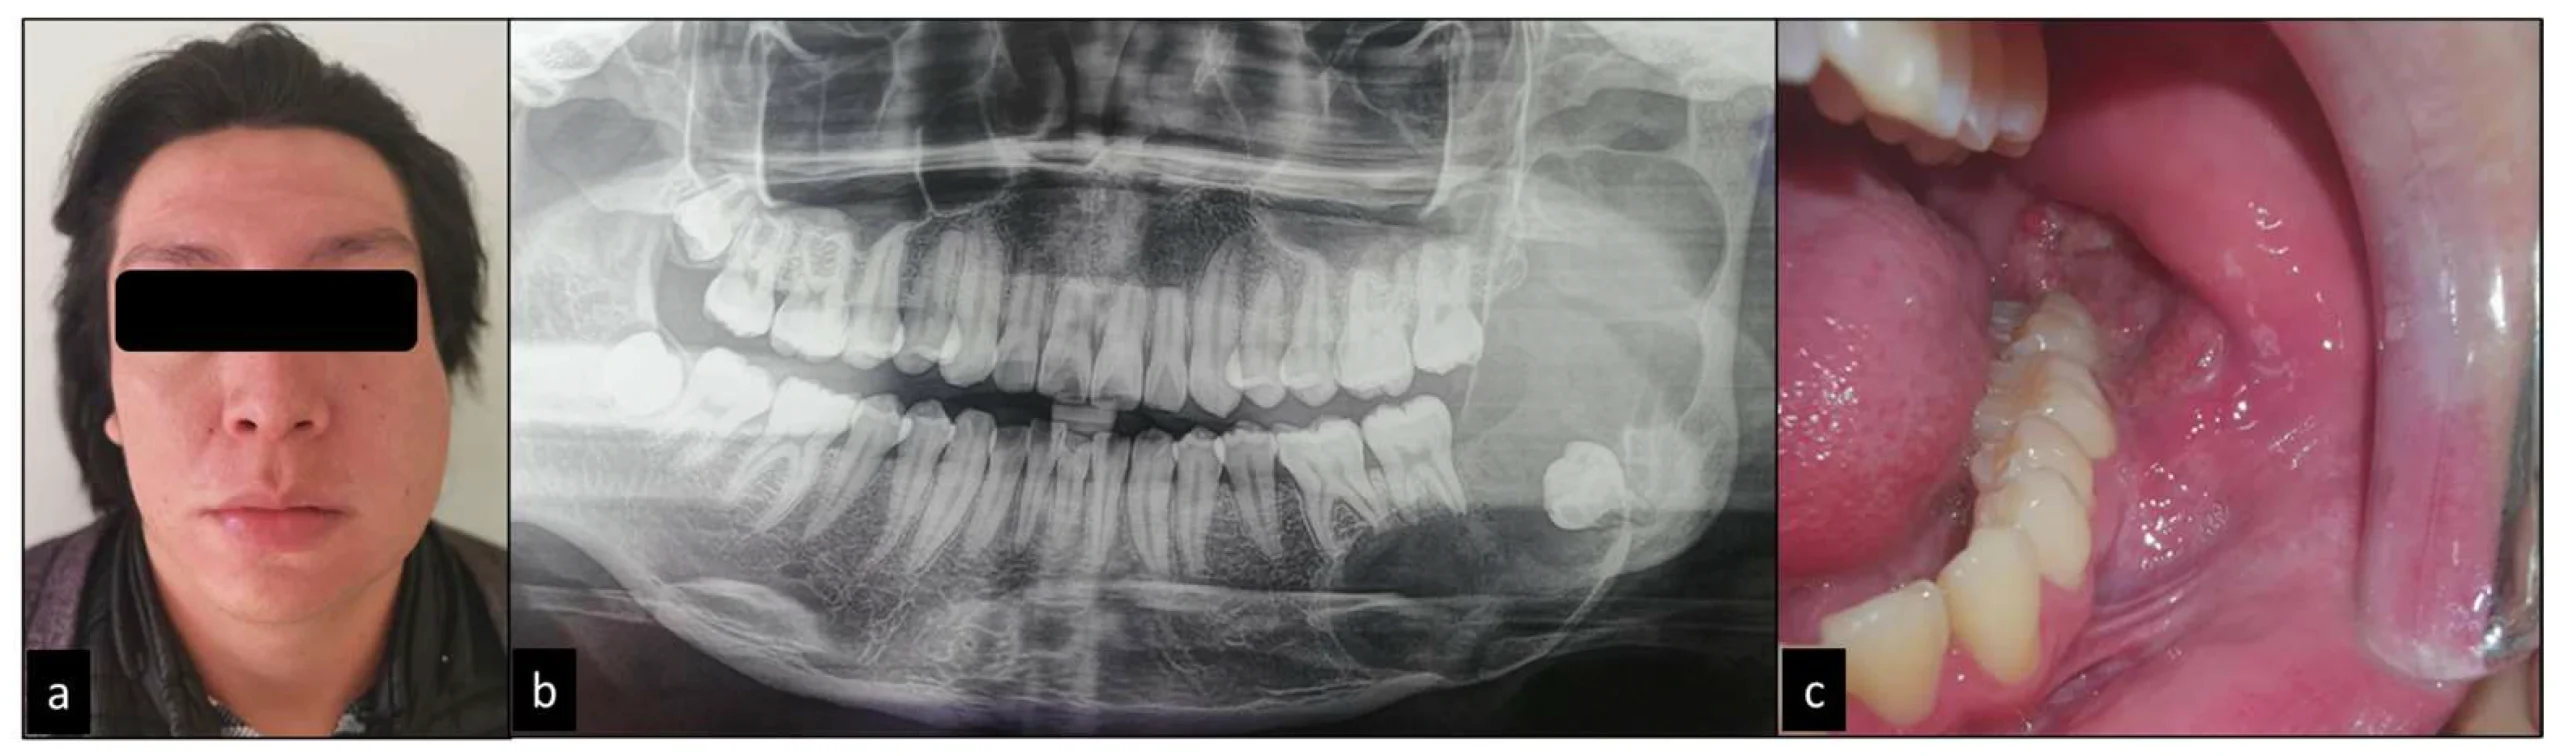

Ameloblastoma adalah tumor jinak odontogenik (berasal dari jaringan pembentuk gigi) yang paling sering ditemukan di rahang, terutama rahang bawah (mandibula) bagian posterior (daerah molar atau